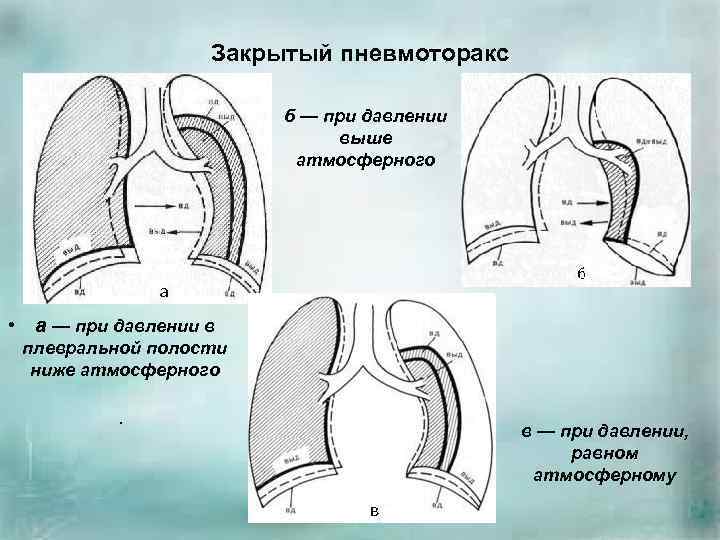

Схемы дыхания: Пневмоторакс на изображениях

Раздел: Необычные решения